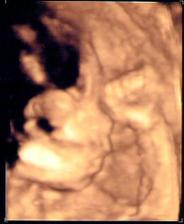

Tohle je albumíček našeho prvního zlatíčka...Jmenuje se JAnička a narodila se 27.11.2007 0,55hod., s mírami 3050g a 46cm, více na http://jaschu.blogspot.com/